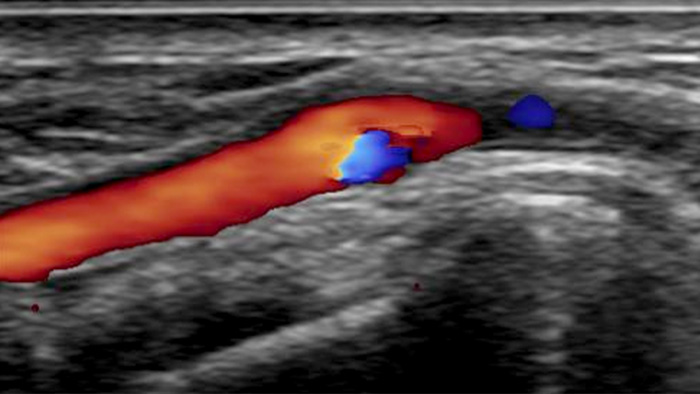

Une visualisation réaliste du système vasculaire artériel est requise pour pouvoir accéder efficacement au système artériel. Notre système d’échographie CX50 intégré fournit des images de haute qualité des vaisseaux et de l’artère radiale afin de permettre des interventions d’accès radiales.

Images de haute définition de vaisseaux avec une vascularité très détaillée pour prendre en charge des stratégies de traitement, une navigation et un suivi de la plus grande précision.